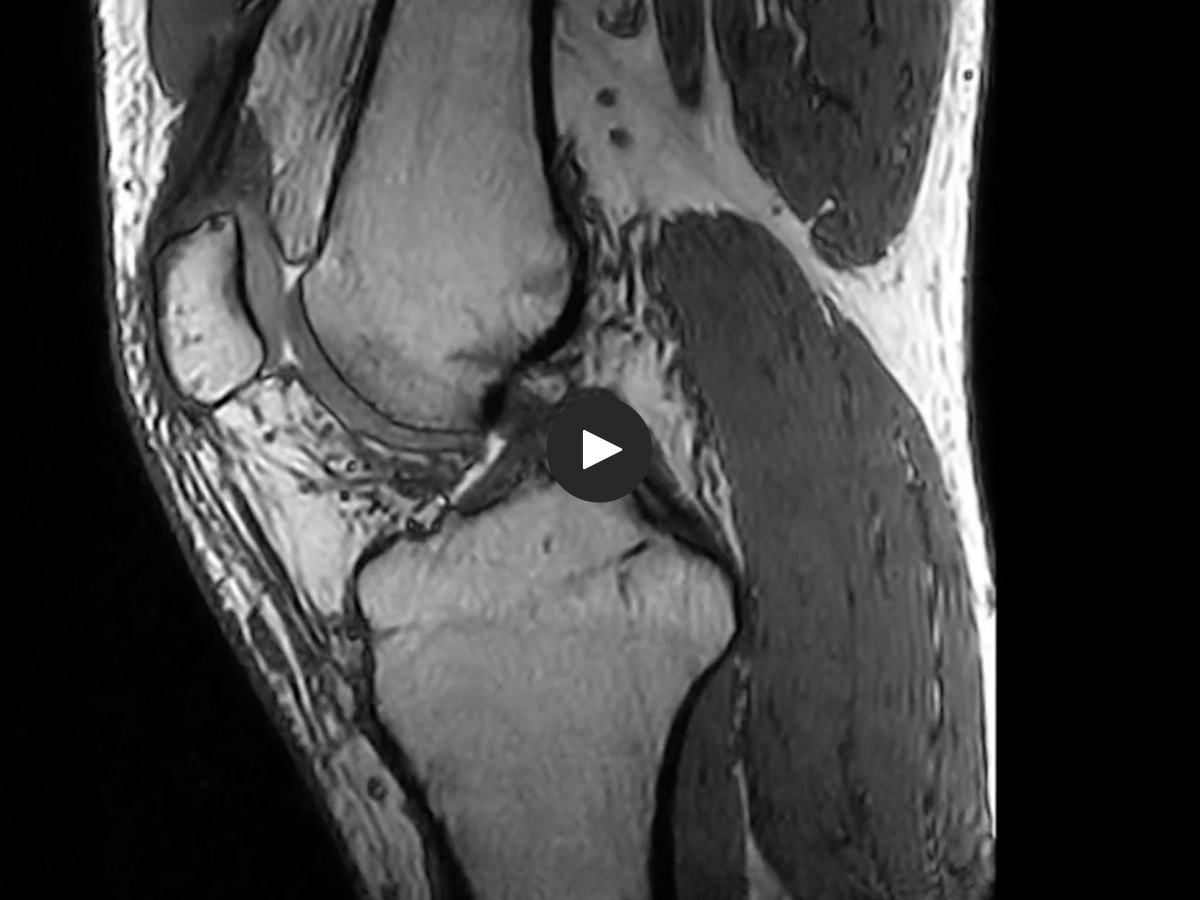

MAR

BETTER - MORE VERSATILE

• The patient population with metal implants is steadily growing; in the USA an estimated 2,4 % of the population or 7,2 mln patients have a hip or knee implant (data Mayo clinic 2014).

• MAR uses a sophisticated gradients management system to suppress or reduce in-plane metal distortions for optimal image quality*.

• MAR improves imaging of post-operative patients.

*Stecco A. et all, Radiol Med. 2019 May;124(5):392-399. doi: 10.1007/s11547-018-0973-5